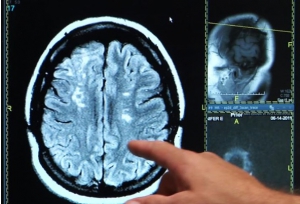

Quelle relation entre AVC et risque de démence, en dehors de facteurs cardiovasculaires en commun ? Si la maladie vasculaire cérébrale a souvent été citée comme un contributeur probable du développement des démences (vasculaires) et de la maladie d'Alzheimer, cette nouvelle étude montre déjà l’association entre athérosclérose et artériosclérose et déficience cognitive. Au-delà, ses conclusions, présentées dans le Lancet Neurology, confirment une relation dose-dépendante entre la sévérité du trouble vasculaire cérébral et le niveau de risque d'Alzheimer.

La maladie vasculaire cérébrale a largement été suggérée comme un facteur de risque possible de la maladie de la maladie d'Alzheimer. On évoque également les démences d'origine vasculaire, impliquée d'ailleurs dans l'Alzheimer. Une étude a documenté qu'une rétinopathie, même légère, c'est-à-dire une maladie des vaisseaux sanguins de la rétine, est associée à un risque accru non seulement de troubles vasculaires dans le cerveau mais aussi de déclin cognitif. Un variant du gène ApoE déjà associé avec le risque de maladie d'Alzheimer, a été documenté comme un agent conduisant à des dommages du système vasculaire cérébral. La maladie vasculaire cérébrale pourrait donc être un « facteur probablement très sous-estimé d'Alzheimer », écrivent les chercheurs.

Les chercheurs du Rush Alzheimer Center (Chicago) ont analysé les données médicales et pathologiques de 1.143 personnes âgées qui avaient fait don de leurs cerveaux dont 478 (soit 42%) diagnostiqués avec la maladie d'Alzheimer. L'analyse des cerveaux montre que,